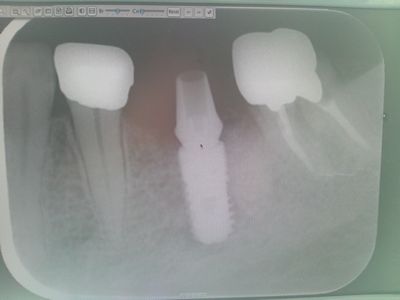

インプラントの埋め込み施術が終わり、早2ヶ月。

骨が形成された頃ということで歯医者に行って来ました。

そこで、びっくりなことが。

歯茎を開いて、土台を作るためにインプラントに杭を打ち込むのですが・・

骨の形成がよくて、インプラントを食い込んでしまった模様・・・。

そこで、再度、骨を砕くのですが・・大変そうでした。

周りの骨を砕いたので、本日、歯の型をとれず、仮土台をつけたのみ。

それがこんな感じ。

ブリッジのためのけずられ王冠を付けられた、左の歯(前側) 虫歯の王冠(奥歯)

はっきり分かります。   神経に薬が入っているか否か。

白いのは薬のためで、これで神経は死んでいます。